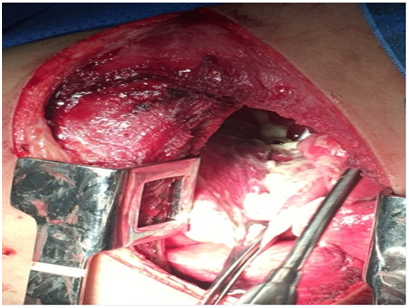

The initial thorax CT (Figure 2) evidenced a considerable increase in the mediastinal planes, with inflammatory areas in the upper and anterior compartments, pleural and pericardial effusion with mediastinal lymph nodes with altered and reactional appearance. The initial cervical CT (Figure 3) showed multiple fluid collections with gaseous foci in the left, parapharyngeal, anterior cervical, right lateral, retropharyngeal and submandibular spaces, with communication between them and a determined extensive mucosal bulging and reduction of the oropharyngeal space. Densification of the muscular planes and glottic region with extensive edema in the visceral space were visualized, characterizing a diffuse and extensive inflammatory process in the cervical region. The patient did not present seropositivity for the HIV virus, exhibited laboratorial values compatible with normal renal function, blood current mixed microbiota with the predominance of Staphyloccuscapitis and sensitivity to all the antibiotics tested, ruling out the presence of super-resistant bacteria. The initial hemogram showed an increased marked number of leukocytes and neutrophils, suggesting a recently established infectious and inflammatory condition. As soon as the diagnostic had been confirmed it was opted for early surgical intervention. The procedures consisted of thoracotomy with the objective of managing pericardial and pleural effusions (Figure 4) to avoid the patient's septic shock; surgical drainage of the right cervical, sublingual, left submandibular, left buccal spaces was also performed plus the extraction of the compromised tooth (Figure 5), indicated as the etiological factor. No airway management surgical procedure was performed. For complete drainage, Penrose and chest drains were installed, which were maintained for 3 and 7 days, respectively. The patient remained sedated for 36 hours postoperatively with or tracheal intubation. The antibiotic therapy of choice was Sodium Piperacillin associated with Tazobactam, 12g and 1.5g per day, respectively. The patient remained under intensive care for 21 days, for postoperative clinical and imaging follow-up control, as well as the remission of signs and symptoms associated with the systemic condition. Currently, the patient is at 6 months of follow-up, in which a satisfactory clinical condition and absence of sequelae are observed.

Figure 4 Right anterior lateral thoracotomy for drainage of pericardial and pleural effusion. It is noticed the presence of whitish crust on the right lung surface.

Mediastinitis is an uncommon and low-incidence complication when compared to other situations such as septic shock, pneumonia and airway obstruction with indication of tracheostomy.4 It is important to emphasize odontogenic infection as an etiological factor and its interaction with cervico-facial spaces. The mortality rate for Necrotizing Fasciitis ranges from 7% to 20%;1 however, when there is an association with DNM, the mortality rate increases to 41%, with a high probability that the patient will die if there is a delay in diagnosis and improper drainage. In the presented case report, the patient required early surgical intervention due to the imminent risk of septic shock. DNM can be classified as an acute or chronic process, with the acute type being more aggressive and symptomatic. It is important to start the diagnostic investigation by the physical evaluation associated with vital signs accompanied by thoracic-cervical imaging and laboratorial tests such as complete blood count and blood culture.4,5 CT scans can demonstrate increases in cardiac and mediastinal boss6,7 as well as evidence of lung collections characteristic of pleural effusion and pericardial effusion, when circumscribed to the cardiac area. These findings are present in the described case report, and the net collection present in the interpleural space evidenced by chest CT resulted in approximately 1000mL in the right thorax. Corroborating current literature,1,4,8,9 cases of Mediastinitis arise mainly when odontogenic infection affects more than one cervical space and submandibular space. In the present case, the composite feature of the involved cervical spaces is evident, since the right cervical, sublingual, left buccal and left submandibular spaces were drained simultaneously with the extraction of the right lower first molar compromised tooth. The presence of unilateral pleural and pericardial effusion was also evidenced, for which the surgical access for anterolateral thoracotomy was performed. This is the most recommended surgical approach for deep surgical treatment in cases of DNM,2,5 although there are other options such as bithoracotomy and median sternotomy, which present the disadvantage of high risk of suture dehiscence and osteomyelitis.9,10 The clinical-surgical therapy should include maintenance of the airways, elimination of the etiological factor, drainage of the deep cervical/thoracic spaces and broad-spectrum antibiotic therapy.1,8 Regarding the interdisciplinary conduct of the presented case report, the patient did not present critical condition as to respiratory activity, reason why no airway management surgical procedure was performed. It was opted for drainage of the fascial spaces affected, thoracotomy for pericardial drainage and debridement of the right thorax and mediastinum, as well as the extraction of the compromised tooth that caused the infectious process. Empirical antibiotic therapy was established immediately after clinical examination and continued for all the hospital stay period. Odontogenic infections, along with tonsillar infections, are among the main predisposing factors for the development of Ludwig's Angina.4 Infections in posterior lower teeth are associated in greater number to this condition due to their straight drainage to the submandibular space, which is located near the retropharyngeal and lateral pharyngeal spaces.8,10 Piperacillinin combination with Tazobactam can be used as first-line therapy to DNM treatment in view of the polymicrobial characteristic of the infection and the broad spectrum of action of these drugs.6 In the presented case report, Sodium Piperacillin associated to Tazobactam demonstrated a satisfactory result, culminating in total Remission of Infection.